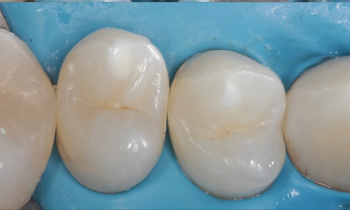

2 работы в портфолио